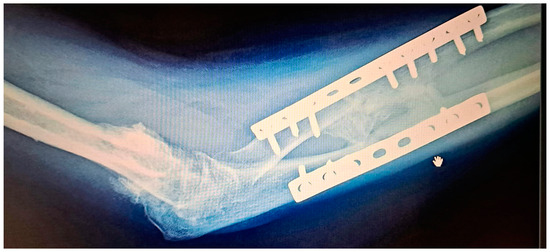

While there is general agreement regarding early intensive rehabilitation, there is no consensus about which is the best protocol. (Figure 4 and Figure 5). The protocols consist of passive and active physiotherapy sessions, splitting in maximum pronation and supination between them [31,44]. The rehabilitation time can sometimes be long and frustrating for the patient. Usually, after the surgery, mobility should be considerably improved. To maintain this result, early mobilization of the forearm (the next day after surgery in prone and supine position) is mandatory. To prevent stiffness, the patient can be placed with the forearm in extreme supination for a few hours, or in pronation position with the help of a cast or splint. The splints are alternately replaced. The patient should know that some degree of motion can be lost during the process due to the retraction of the soft tissue or insufficient mobilization, but if there is no recurrence, the results are very good.

Figure 5. (a) Pronation and (b)supination movement after a few months from the surgical resection of the synostosis.